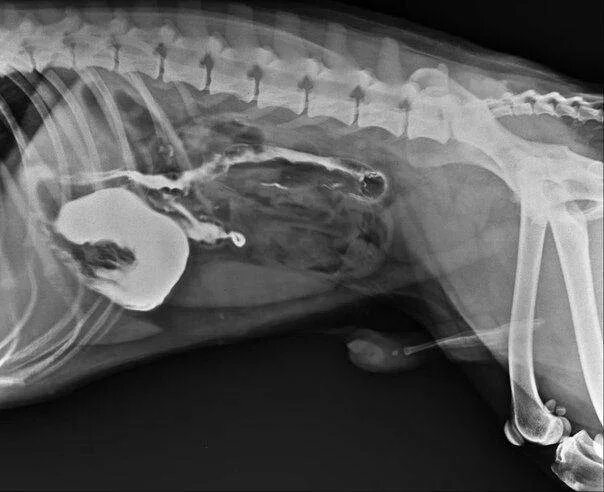

Как собачка проглотила жука